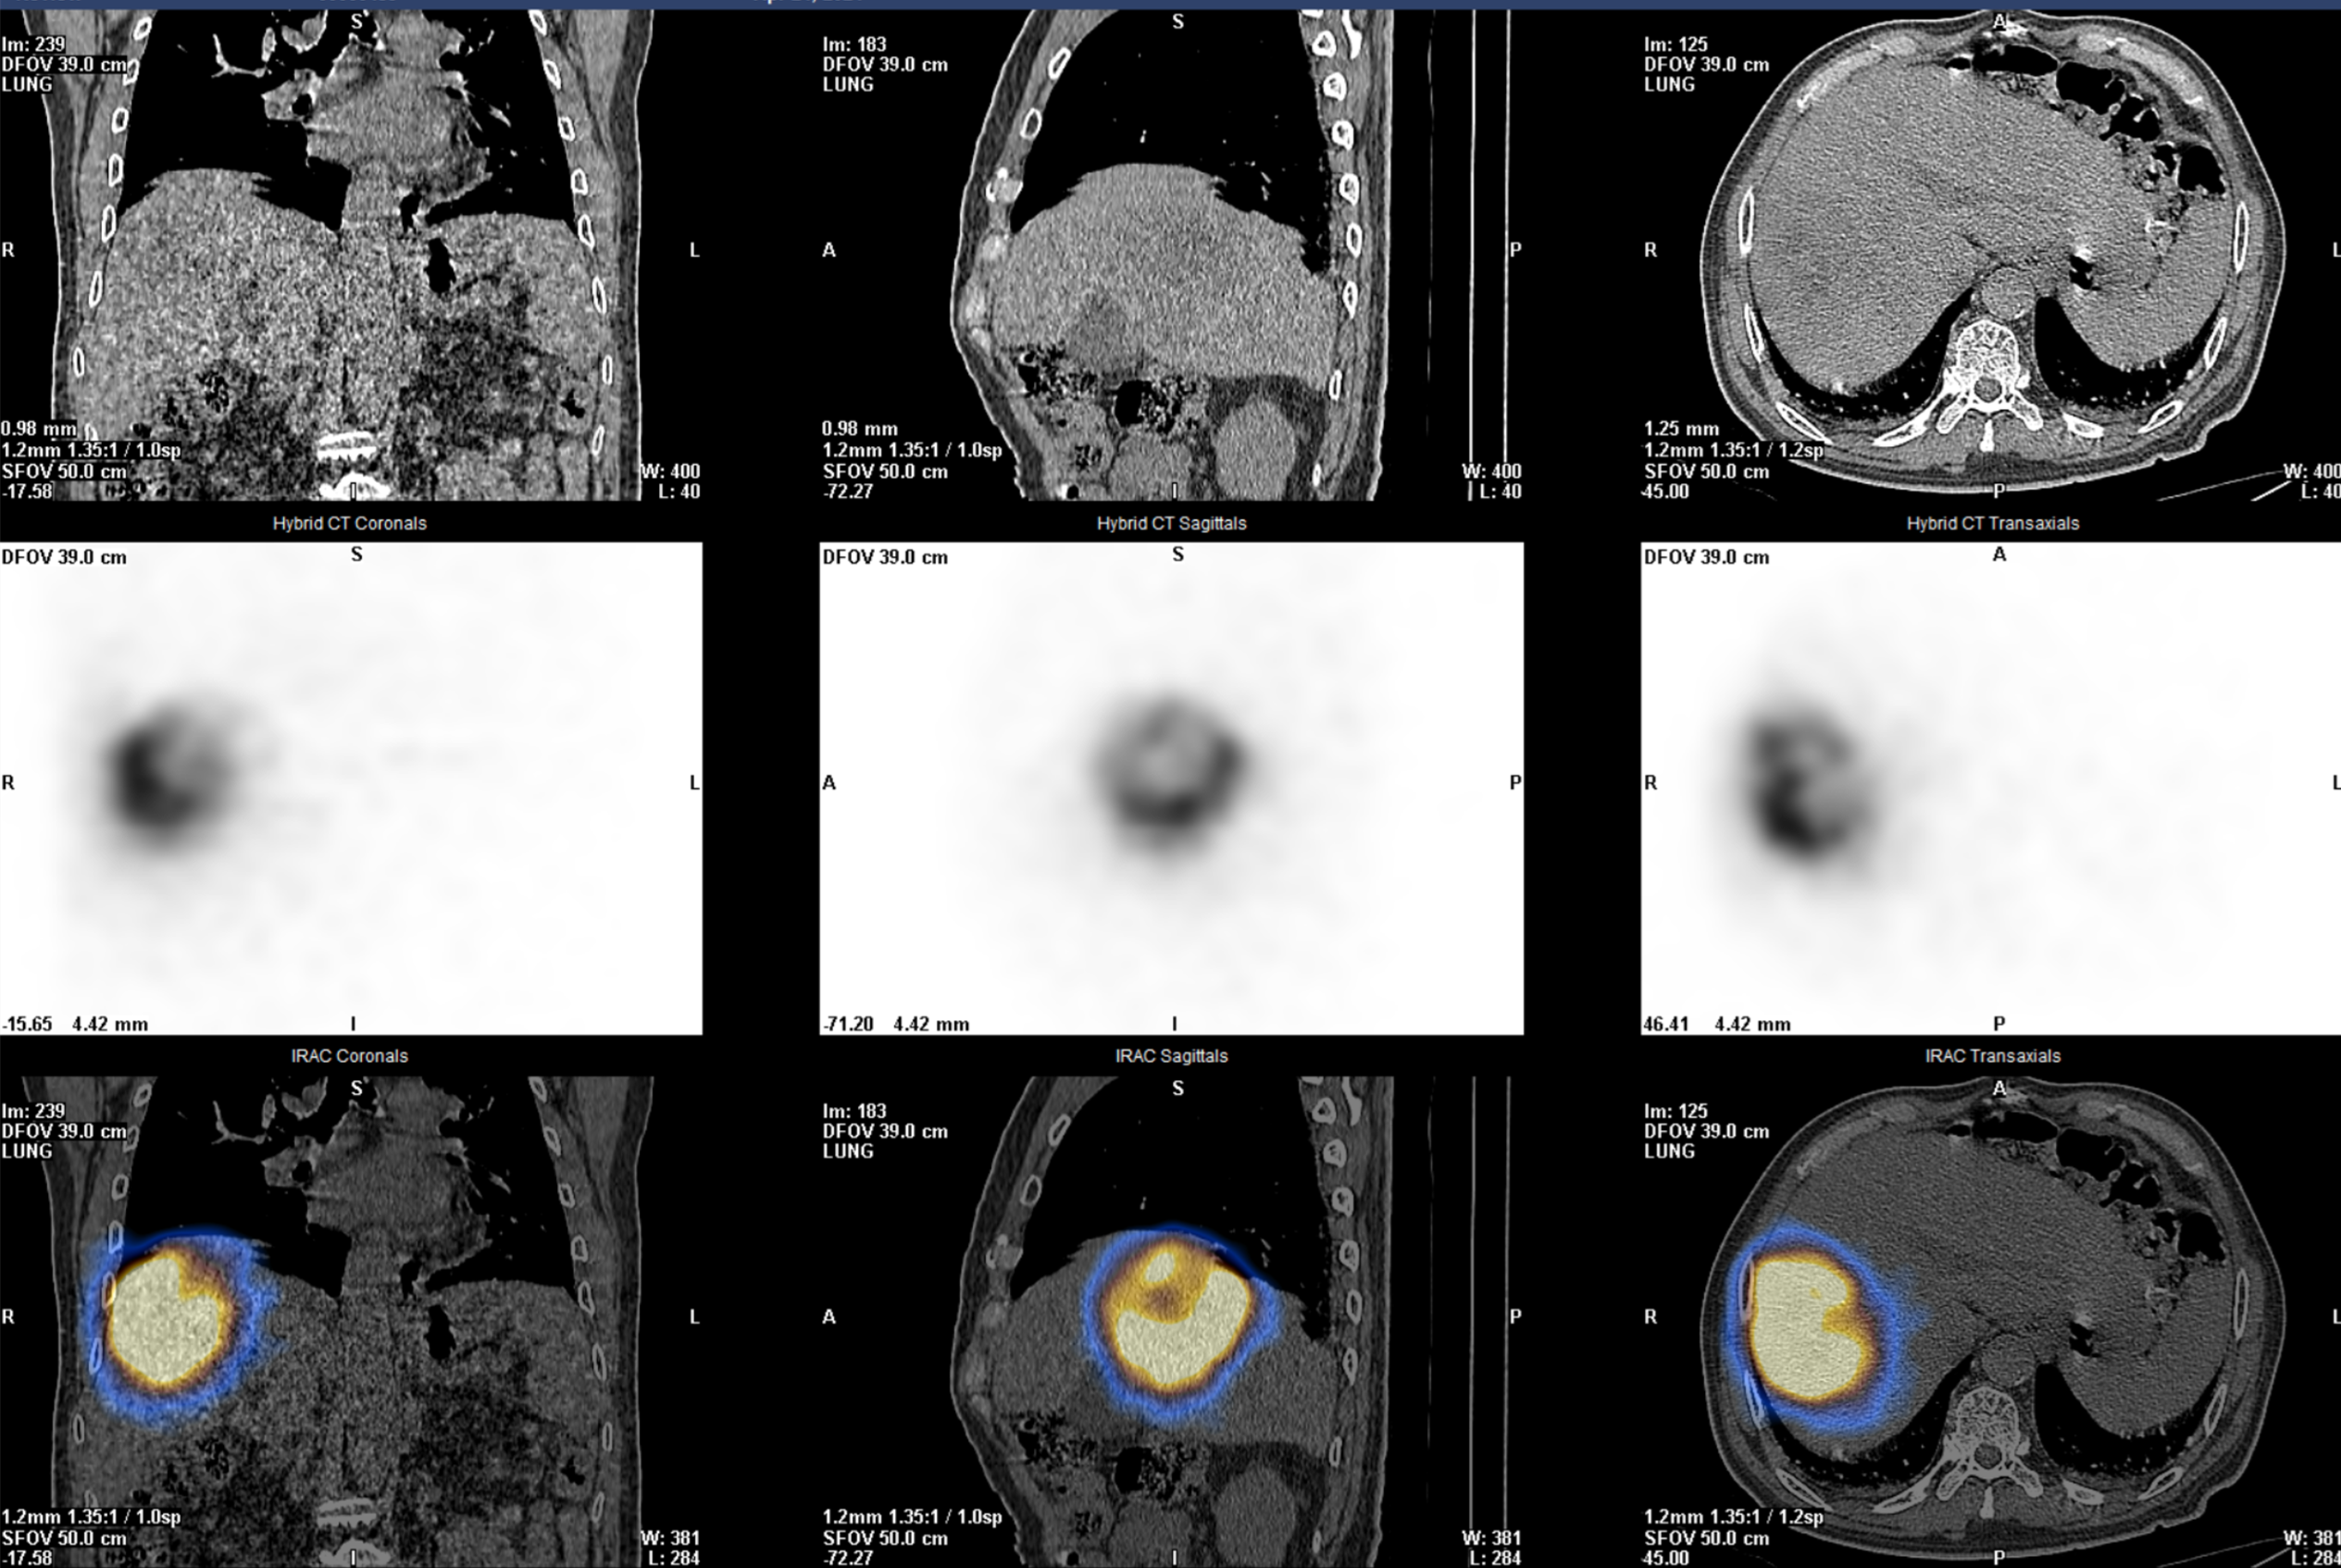

术后:Y90微球在肿瘤内沉积良好